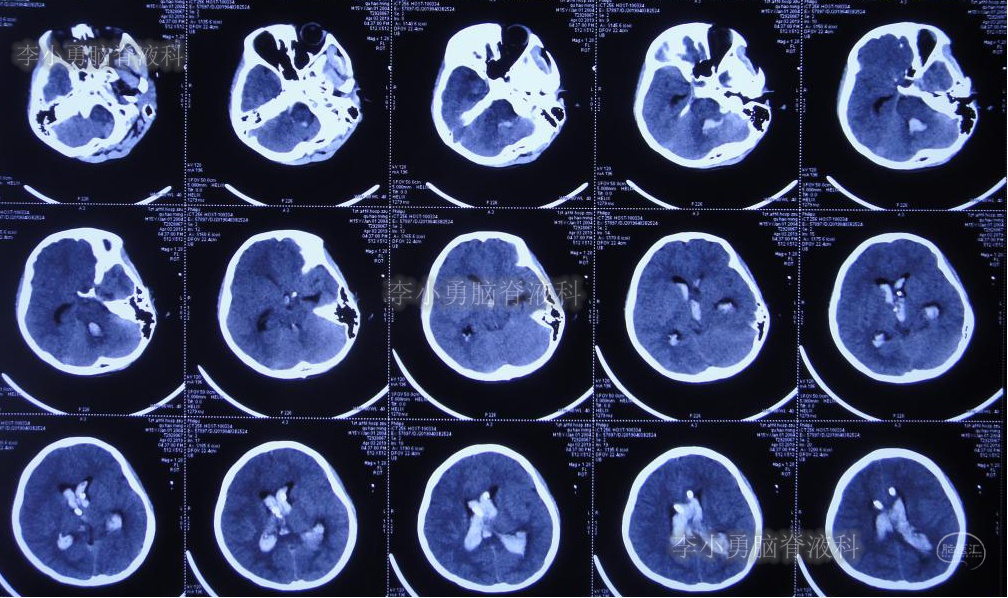

入院当日行头颅CT(图-10):脑室内“动脉瘤切除术”后改变,术区可见引流管影,脑室扩大。

图-10:2019年5月7日头颅CT:引流术后,脑室扩大

入院次日即2019年5月8日,进行了右侧脑室外引流术,并保留原来脑室外引流管(注:脑室内有两根管)。术后常规复查头颅CT(图-11)。

图-11:2019年5月9日头颅CT:引流出淡黄色脑脊液

图-12:2019年5月16日复查头颅CT:左侧颞角扩大并周边水肿

图-14:2019年5月28日头颅CT:脑室较前缩小,水肿亦减轻

但是患者逐渐开始出现头部不适,轻度头痛,且近期记忆力很差。右侧脑室外引流术后25天即2019年6月3日,再次复查头颅CT(图-15):右侧颞角再次扩大并周边水肿明显,术区水肿。

图-15:2019年6月3日头颅CT:左侧颞角扩大并周围水肿

图-16:2019年6月12日头颅CT:左侧颞角进一步扩大并水肿加重

图-17:2019年6月13日头颅CT:拔除原术区引流管

拔管后患者头痛逐渐加重,记忆力逐渐减退。于拔管后11天即2019年6月24日复查头颅CT(图-18):左侧颞角积水加重。

图-18:2019年6月24日头颅CT:左侧颞角扩大加重

次日即2019年6月25日,进行了左侧颞角外引流术;术后次日复查头颅CT(图-19):左颞角引流管位置良好。

图-19:2019年6月26日头颅CT:左侧颞角引流术后